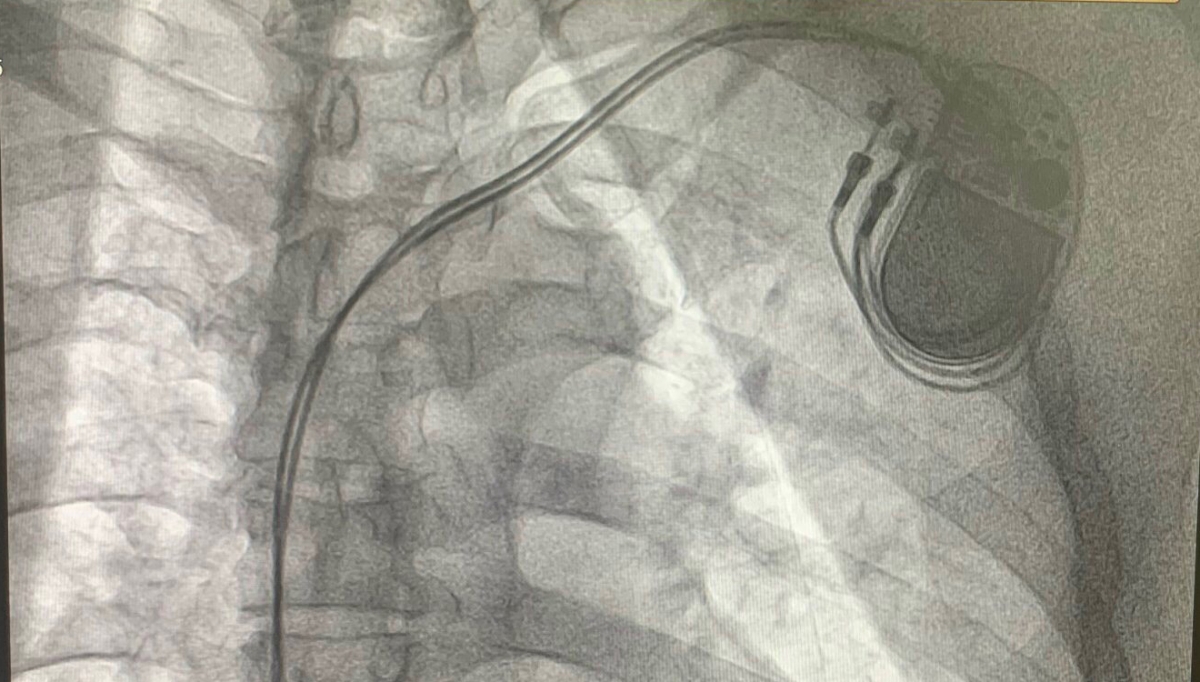

Trước đó, một cụ ông 91 tuổi nhập viện trong tình trạng nhịp tim chỉ còn 39 lần/phút. Bệnh nhân cũng có nhiều bệnh lý nền như tăng huyết áp, viêm dạ dày, trào ngược dạ dày - thực quản, viêm phế quản mạn. Các bác sĩ Khoa Tim mạch can thiệp - Lão khoa Bệnh viện Đa khoa tỉnh Quảng Ngãi đã hội chẩn và quyết định phẫu thuật đặt máy tạo nhịp tim vĩnh viễn cứu bệnh nhân.

Thạc sĩ, bác sĩ Nguyễn Hồng Vương, Khoa Tim mạch can thiệp - Lão khoa, cho biết ca phẫu thuật gặp nhiều khó khăn do bệnh nhân lớn tuổi, cơ ngực mỏng, dễ nhiễm trùng. Ngoài ra, bệnh nhân bị viêm phế quản mạn nên quá trình thao tác phải hết sức thận trọng để tránh biến chứng tràn máu, tràn khí màng phổi.

Sau gần 2 giờ, ê kíp đã hoàn thành ca phẫu thuật. Hiện, nhịp tim bệnh nhân đã ổn định ở mức 60 lần/phút, sức khỏe dần hồi phục, sinh hoạt như bình thường.